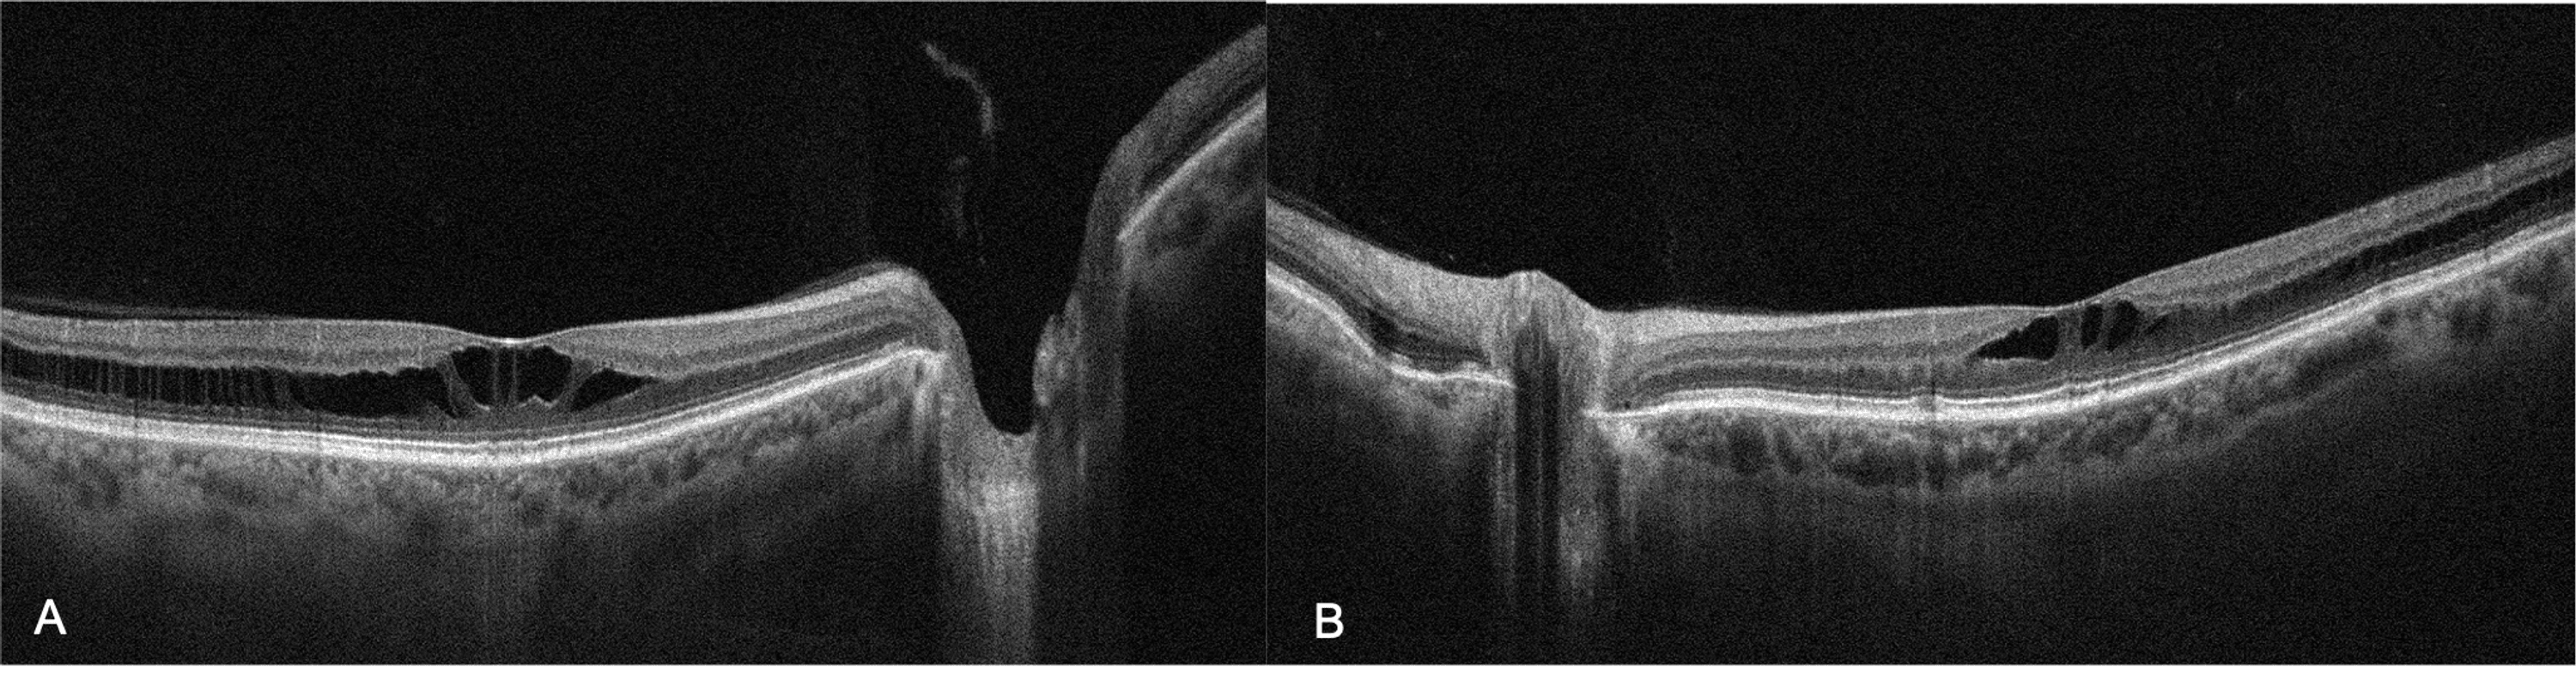

Outer macular retinoschisis (Fig. 3(b), star) alone in an eye with... Download Scientific Diagram

Figure 1 from En Face Optical Coherence Tomography of Bilateral Myopic Macular Retinoschisis Retinoschisis Bilateral Retinoschisis is a condition that occurs when a layer of the retina splits into two. In some cases, the condition is present at birth. Retinoschisis is a condition in which an area of the retina (the tissue lining the inside of the back of the eye that transmits visual signals to the. The retina is the tissue inside the back. Retinoschisis Bilateral.

(PDF) Multimodal imaging of bilateral macular hole in Xlinked retinoschisis Retinoschisis Bilateral The retina is the tissue inside the back of the eye that. Retinoschisis refers to the separation of the layers of the retina. It can cause problems with the central or peripheral vision. Senile retinoschisis is a microcystoid degeneration of the neurosensory retina, with splitting at the outer plexiform layer of the retina. It’s a genetic disease of the retina. Retinoschisis Bilateral.

Bilateral macular holes in Xlinked retinoschisis now the spectrum is wider. Abstract Retinoschisis Bilateral The juvenile form is the more serious form of. In some cases, the condition is present at birth. Usually, and almost always with the juvenile form, both eyes are affected (bilateral). Retinoschisis is a condition in which an area of the retina (the tissue lining the inside of the back of the eye that transmits visual signals to the. Senile. Retinoschisis Bilateral.